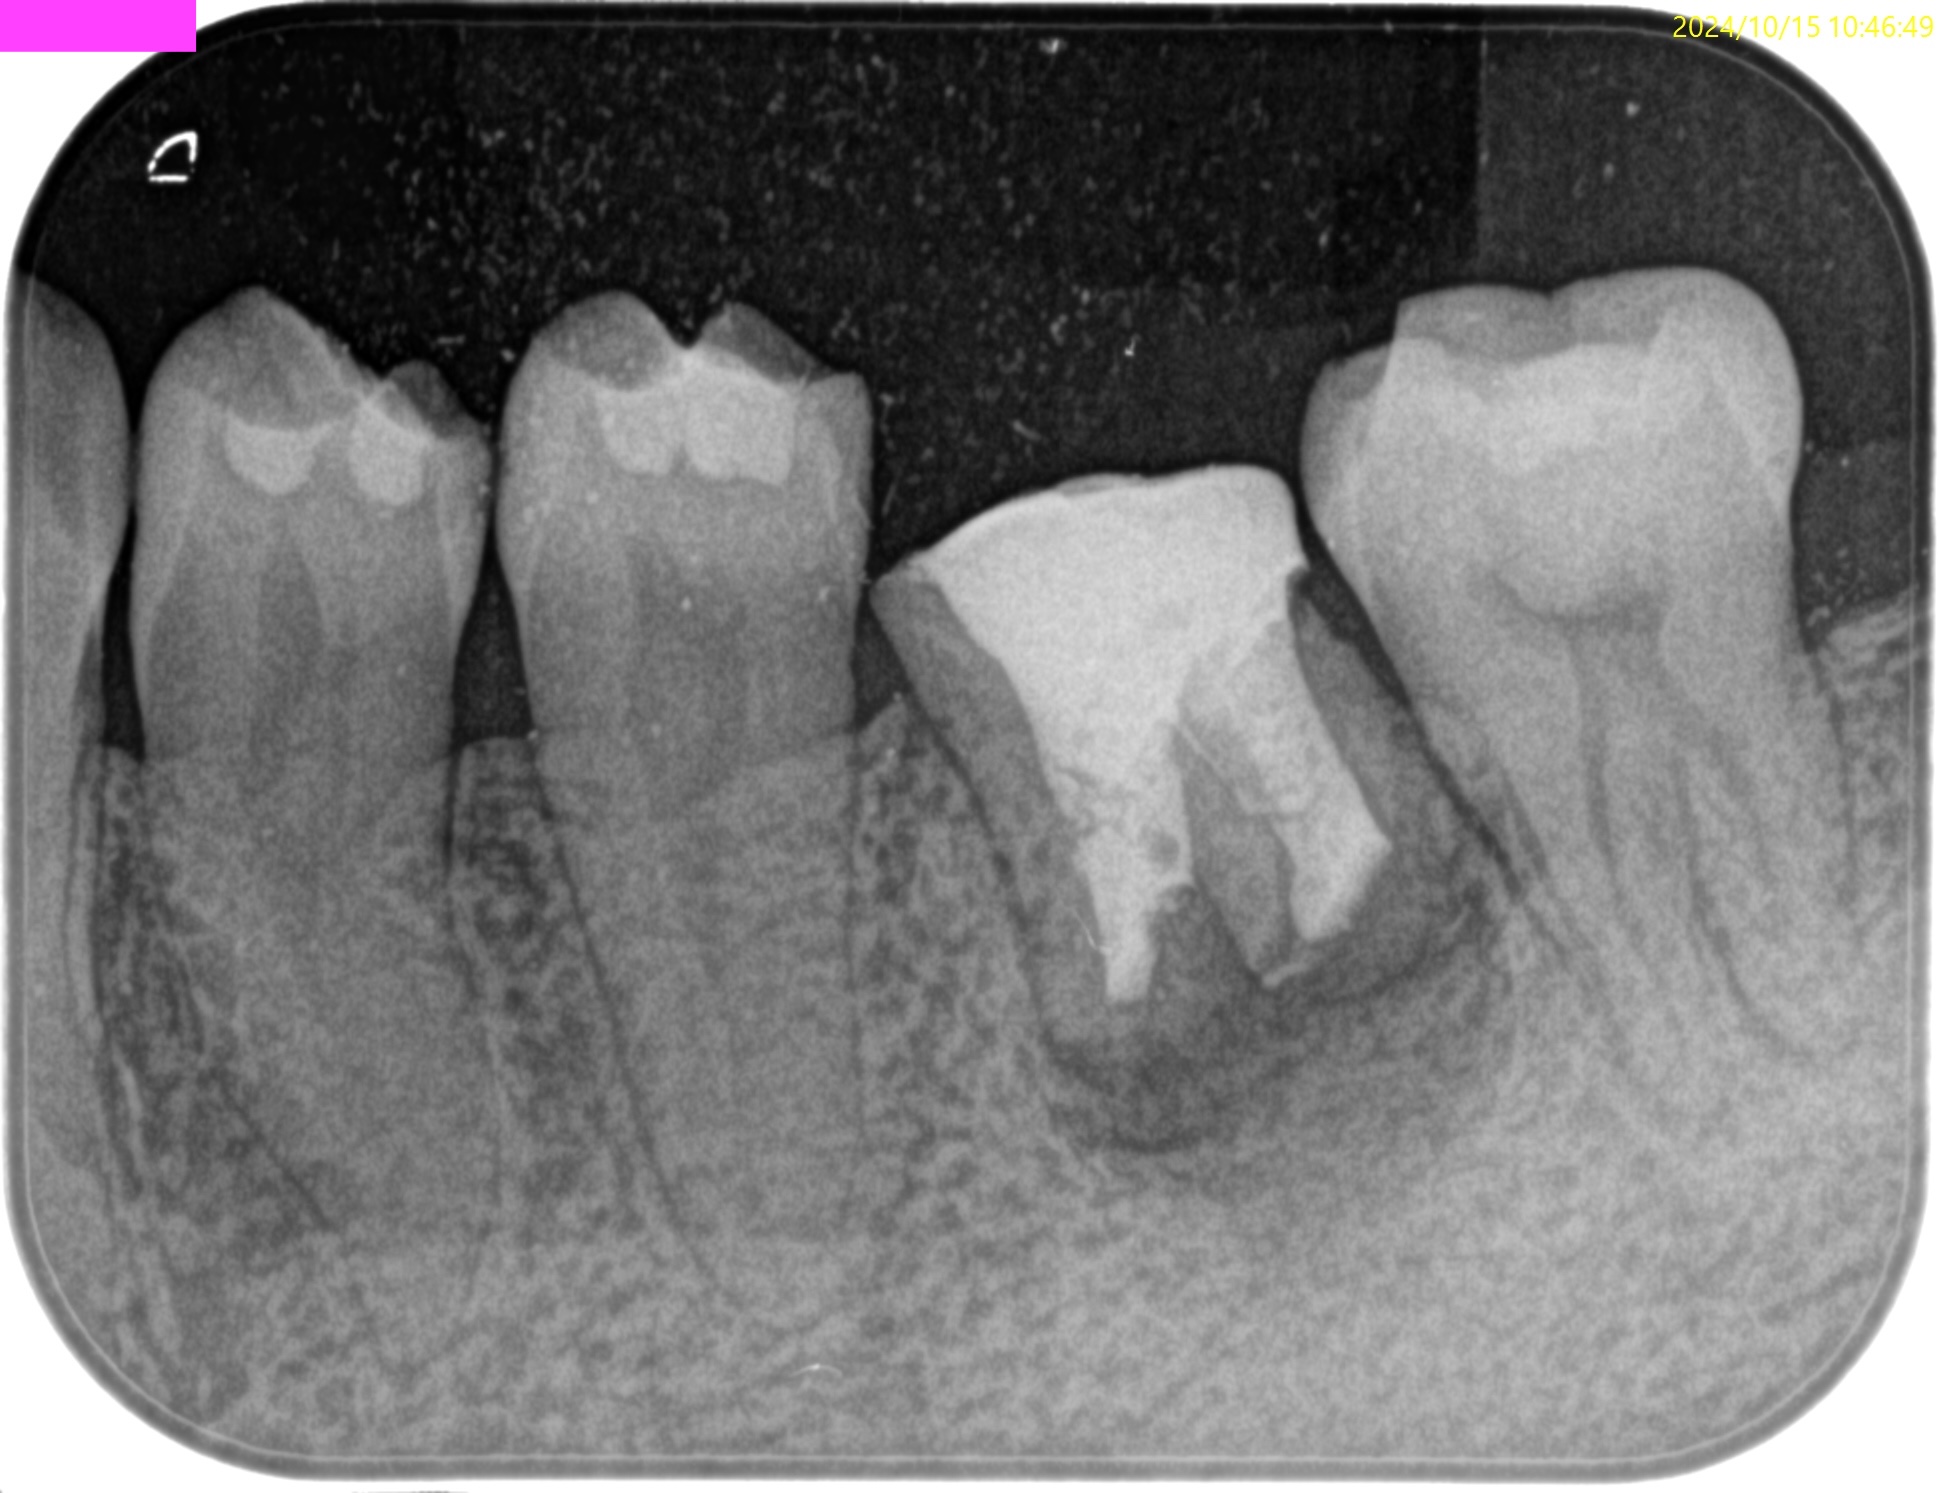

術後にPA, CBCTを撮影した。

M

D

問題はないだろう。

以下のようにPA,CBCTはなった。